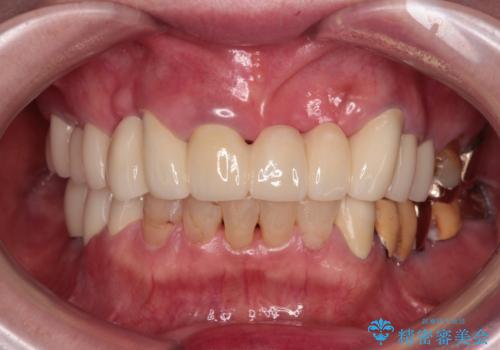

前歯をきれいにしたい インプラントや部分矯正を用いた総合歯科治療

- 抜歯の必要な前歯や、以前治療した前歯のクラウンの外観を気にして来院された患者様です。

上顎犬歯や下顎大臼歯は、必要なところはインプラントを埋入することとしました。

クラウンが不適合であったり、根管治療の必要なほどの痛みのある歯であったり、見た目の気になる前歯などをオールセラミッククラウンに補綴治療を行うこととしました。

処置を予定していた歯を仮歯に変えた時点で、下顎前歯の部分矯正を行うかどうかを尋ねたところ、折角なので行いたいと言うことでしたので、矯正治療を行うこととしました。

インプラント埋入や根管治療治療など、治癒に一定の期間を要する処置の合間に矯正治療を行うことで、効率的に治療を進めて行くことができました。